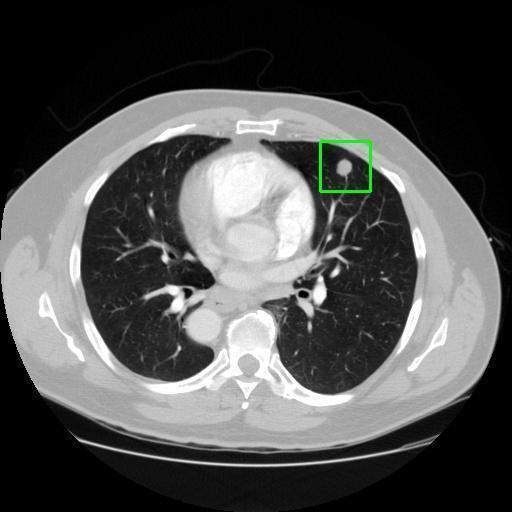

We developed an AI-based system using deep learning models for analyzing lung CT scans to detect and classify pulmonary nodules. We chose the YOLOv11 architecture for its enhanced object detection capability and adapted it specifically for medical imaging, incorporating pixel-level precision and severity classification.

Classification into three severity levels with colored bounding boxes.

Successfully built and deployed an AI model (YOLOv11) capable of detecting lung nodules in CT scans with high accuracy and real-time performance.

Designed a severity classification system that categorizes nodules into null, moderate, and severe using colored bounding boxes, assisting in rapid clinical decision-making.